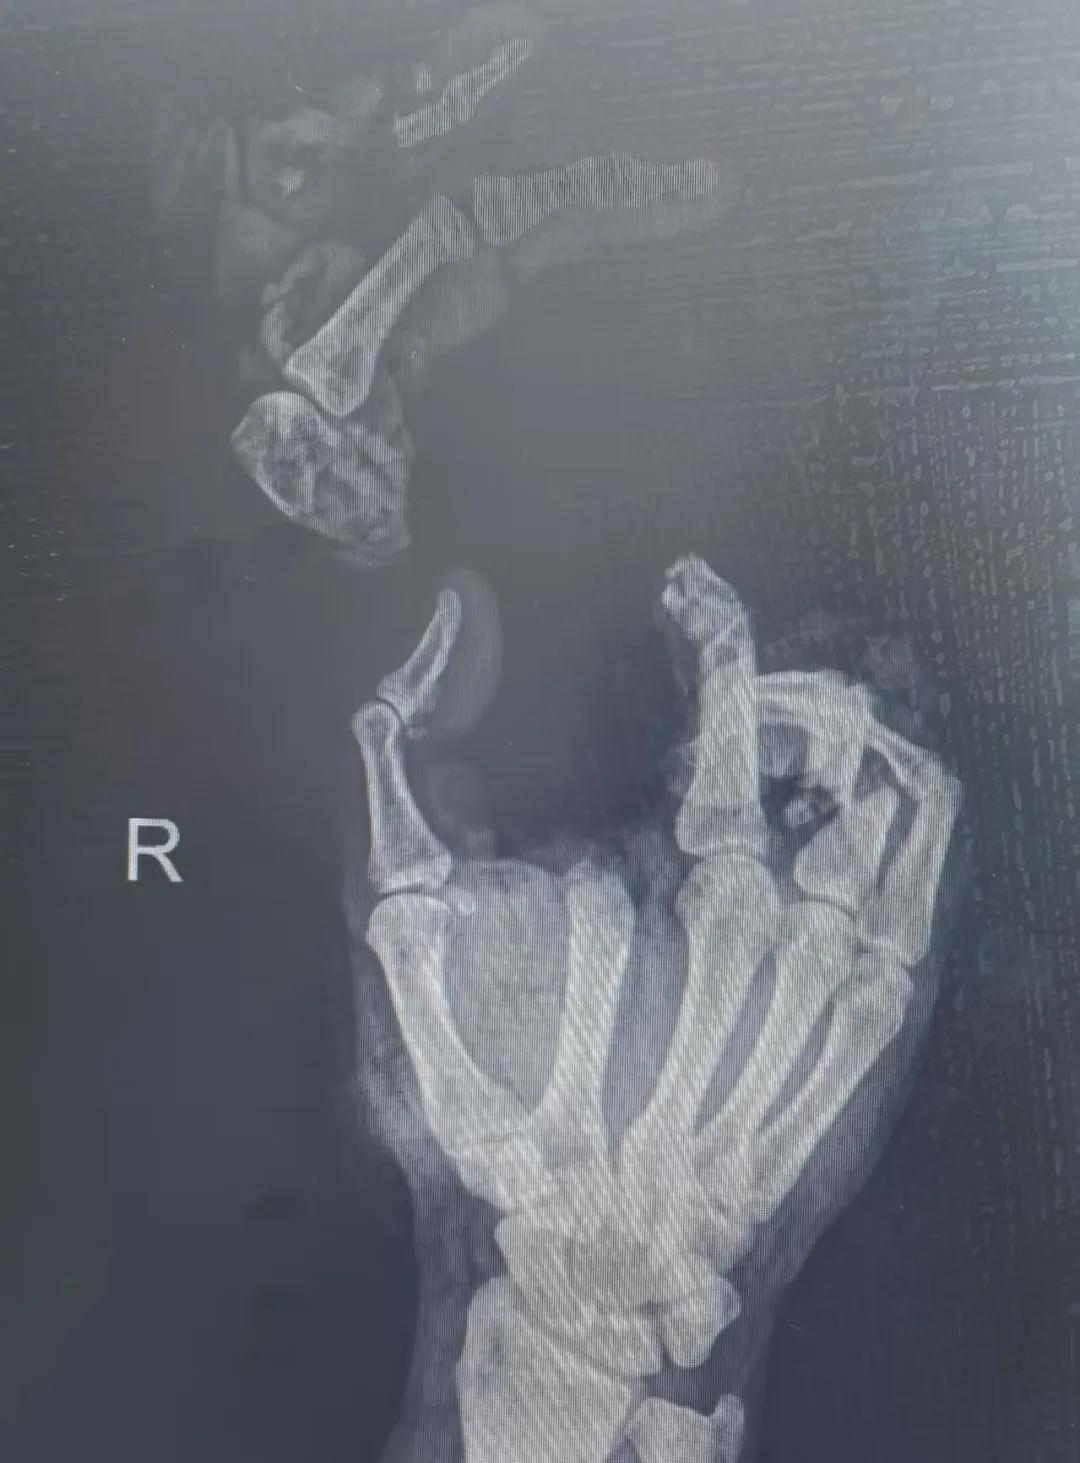

5月20日,市二院顯微外科燒傷整形科收治了3例因麥收被農(nóng)機“咬傷”、農(nóng)具劃傷的患者。其中,56歲的劉某在收麥子時被打谷機皮帶絞傷右手,致手掌、食指、中指、環(huán)指嚴重毀損傷,骨、關(guān)節(jié)外露,因當?shù)蒯t(yī)院無法治療,被家人緊急送往市二院顯微手足燒傷整形外科救治。“當時整個右手血肉模糊,看上去都是爛的,我以為這個手是肯定保不住了。”患者家屬回憶當時的場景仍然膽戰(zhàn)心驚。

患者入院后,經(jīng)X線檢查及創(chuàng)面檢查,醫(yī)生診斷為右手食指、中指及環(huán)指旋轉(zhuǎn)撕脫性離斷。接診的顯微手足燒傷整形外科醫(yī)護人員立即完善了各項術(shù)前準備,并安排急診手術(shù)。因創(chuàng)面污染嚴重以及離斷肢體損傷程度較重,手術(shù)歷時近10小時。在沈衛(wèi)軍主任的帶領(lǐng)下,科室團隊成功為其進行了創(chuàng)面擴創(chuàng)、斷肢再植術(shù),術(shù)后患指血運良好,在進一步觀察治療中。